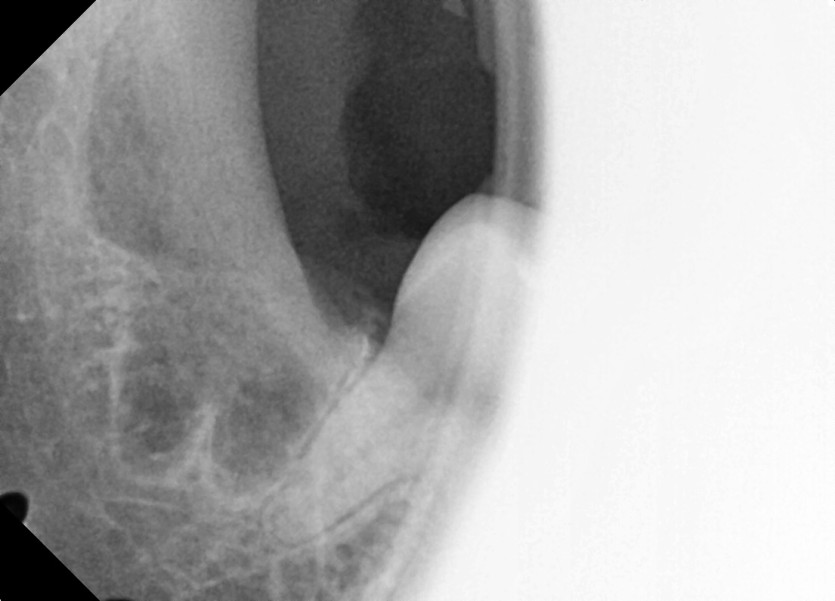

#18,48 사랑니 발치

구강 외과 전문의가 당일 발치했습니다.